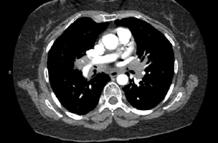

A 58-year-old female with recently diagnosed COVID-19 pneumonia was found to have a dry cough and dyspnoea in the setting of persistent bilateral hilar and mediastinal lymphadenopathy associated with bilateral nodular infiltrates. Of note, she immigrated to the USA from India 10 years prior, with the most recent travel to India 2 years ago. Quantiferon testing upon return to the USA was negative at that time. Workup included bronchoscopy with endobronchial ultrasound revealing non-caseating granulomas with negative stains for acid-fast bacilli (AFB). She was diagnosed with Stage 3 sarcoidosis and initiated on prolonged steroid taper with improvement of symptoms. With taper of steroid dose, however, she developed lymphocyte-predominant exudative effusion with negative cultures, and was reinitiated on a protracted steroid course with rapid symptom resolution. At 4-month follow-up, she had worsening CT findings upon steroid taper, and was started on azathioprine. One month later, she required hospital admission for worsening dyspnoea and fatigue. She was noted to be febrile, tachycardic, and tachypnoeic with worsening

hypoxia. Subsequent CT chest showed progression of bilateral nodular infiltrates with new right upper lobe consolidation and air bronchograms concerning for multifocal pneumonia (Figure 1). Incidentally, she was also noted to have calcified splenic granulomas. She developed rapid clinical deterioration, ultimately requiring mechanical ventilation, pressor support, and continuous renal replacement therapy. Repeat bronchoscopy revealed diffuse alveolar haemorrhage with multiple AFB smears positive for Mycobacterium tuberculosis. She was immediately initiated on quadruple therapy, but unfortunately, despite treatment, developed refractory shock and passed away 2 weeks after initial presentation.

A) Initial adenopathy with peripheral patchy ground glass opacities in the right lung following COVID-19 pneumonia. B) Persistent bulky adenopathy 1 year after initial presentation. C) Extensive nodularity throughout the right lung with increasing confluent opacities in the right upper lobe and stable mediastinal lymphadenopathy 2 years after initial presentation. D) Tuberculosis superimposed on sarcoidosis with progression of nodular infiltrates, worsening right upper lobe consolidation, and air bronchograms with incidental calcified splenic granulomas (not pictured).

Figure 1: CT progression of patient’s sarcoidosis and tuberculosis.